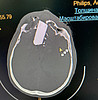

Как рассказал врач-нейрохирург Никита Иньков, осколок диска был очень большого размера – длиной 6 см, шириной 5 см и толщиной 2 см – он сломал лобную кость, повредил оба полушария головного мозга. По результатам осмотра врачей и компьютерной томографии пациенту были диагностированы: открытая черепно-мозговая травма, ушиб головного мозга тяжелой степени с формированием внутримозговой гематомы, массивное травматическое кровоизлияние, пневмоцефалия (скопление воздуха внутри черепа), многофрагментарный депрессионный перелом лобной кости с внедрением инородного тела и отломков в твердую мозговую оболочку и вещество лобной доли, ушиб обеих орбит и обоих глазных яблок и другие повреждения.

– В экстренном порядке была проведена операция, – декомпрессивная трепанация черепа в лобной области, удаление инородного тела, костных отломков, внутримозговой гематомы, пластика твердой мозговой оболочки основания черепа. Сложность операции заключалась в том, что, помимо наличия большого инородного тела, у пациента были повреждены кости основания черепа, твердая мозговая оболочка, а также саггитальный синус и сосуды головного мозга. Это вызвало массивное кровотечение – пришлось подключать аппарат для аутотрансфузии крови пациента. К счастью, все получилось, операция прошла успешно, и это результат командной работы, в том числе врача-офтальмолога Надежды Мартынович и анестезиолога-реаниматолога Олега Чагина. Пациент в удовлетворительном состоянии выписан под амбулаторное наблюдение отоларинголога и невролога. Впереди еще очень долгий путь восстановления, – поделился Никита Иньков.